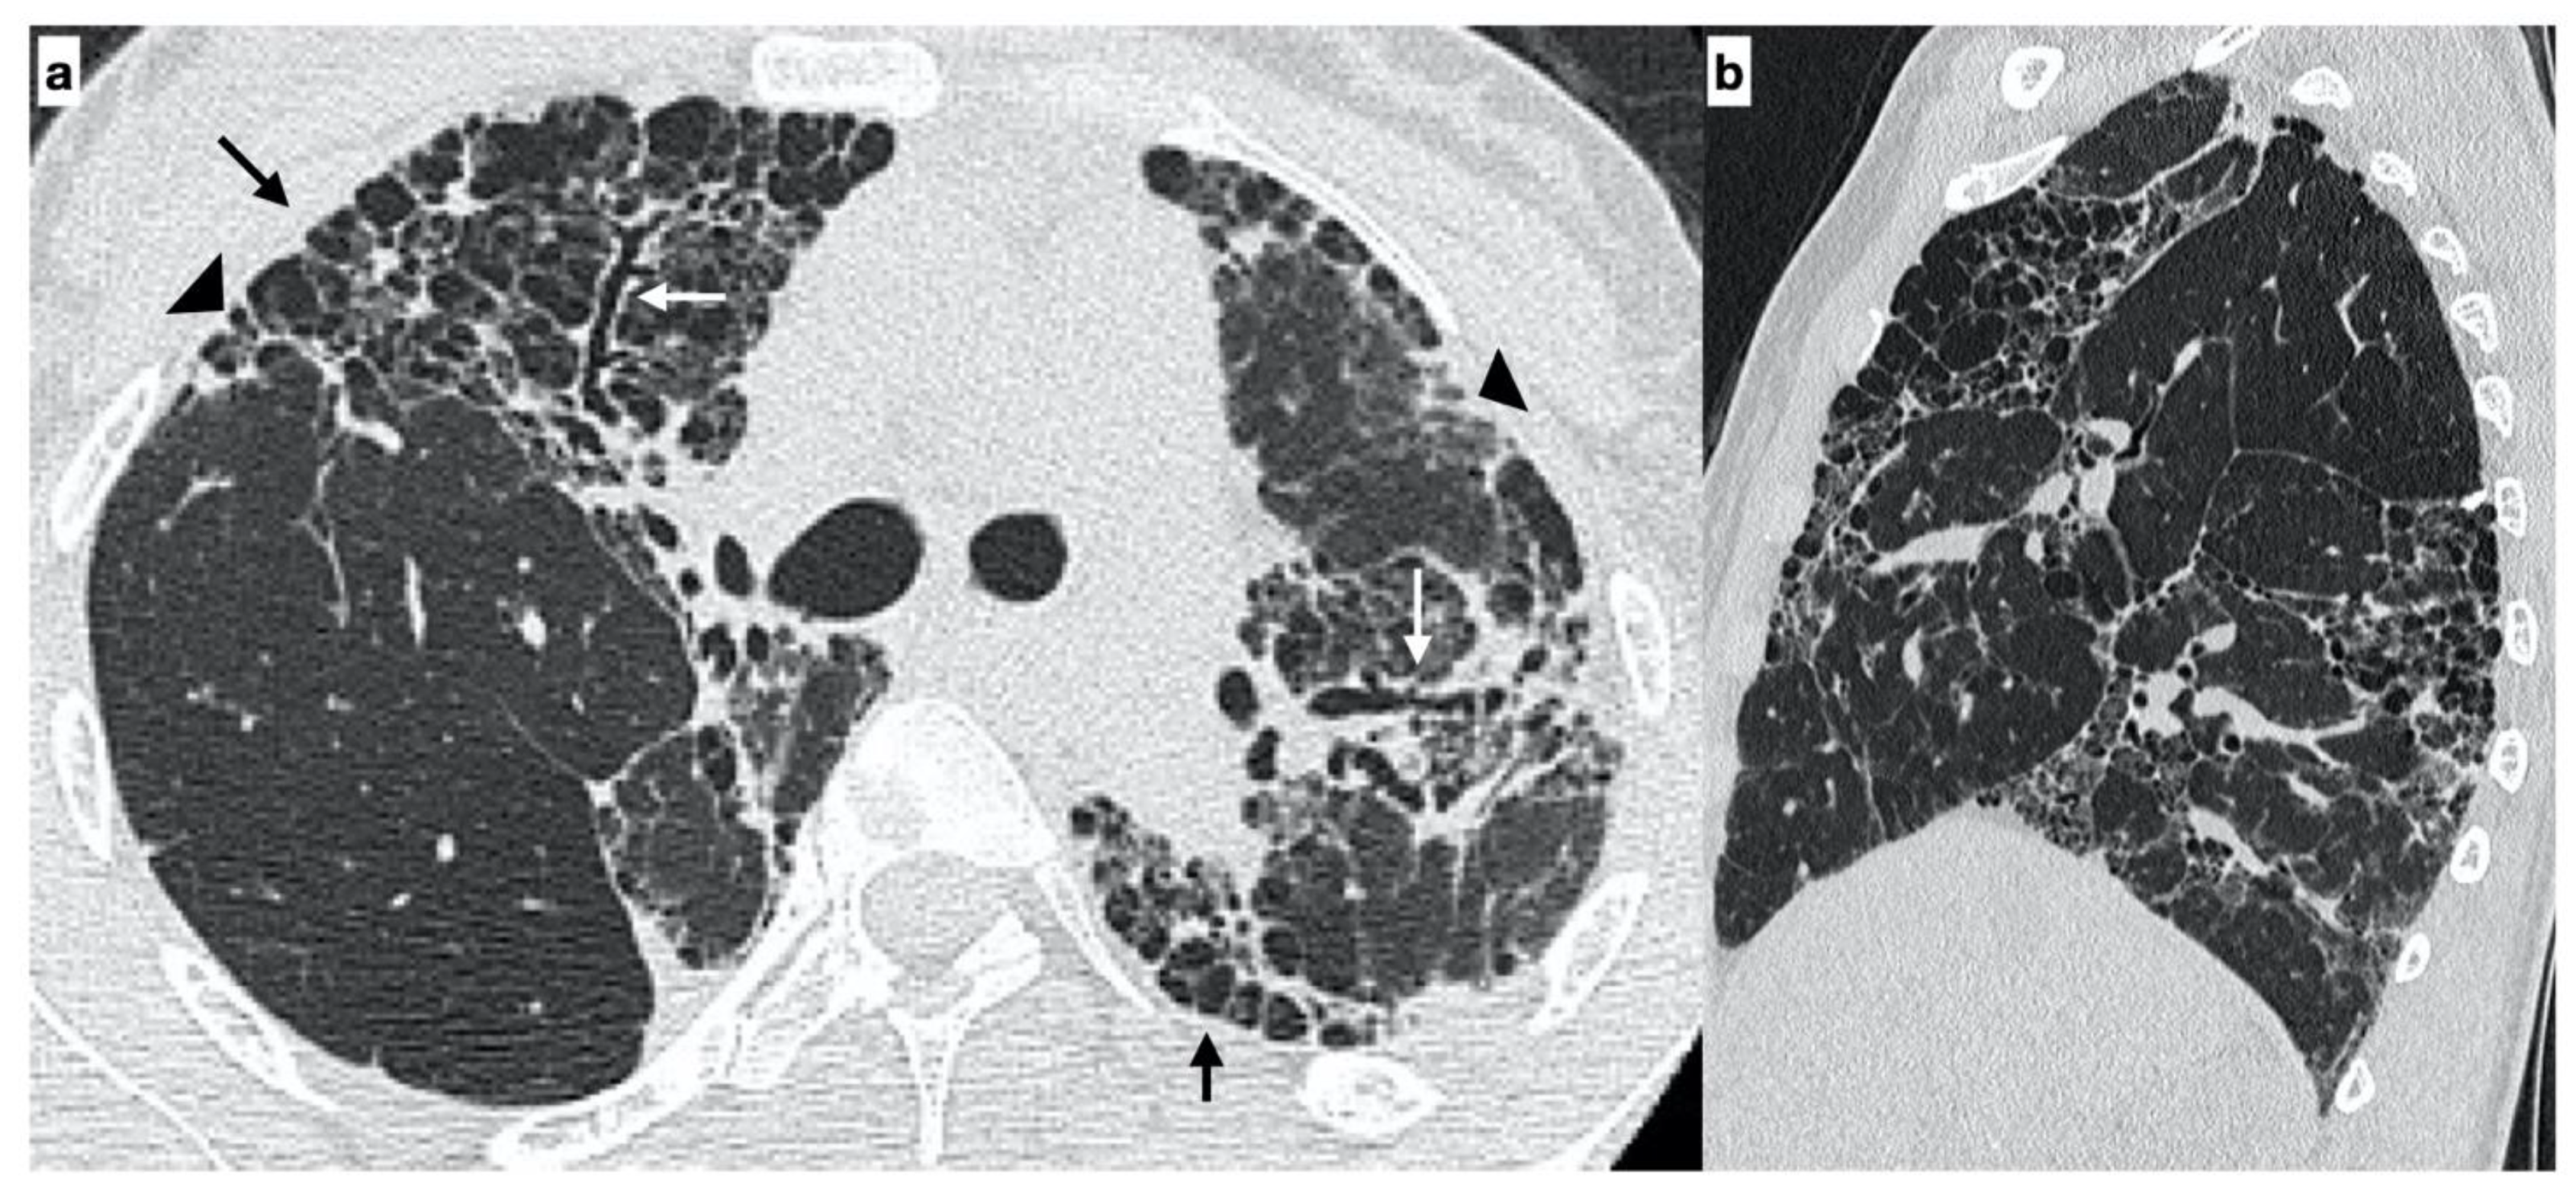

At diagnosis, there was a statistically significant difference in the HRTC pattern between the two groups: sporadic IPF patients had a predominantly typical UIP pattern compared to familial IPF patients (60.0% vs. 21.1%, respectively). There was a predominance of an alternative diagnosis HRTC pattern in familial IPF compared to sporadic IPF (31.6% vs. 2.2%, respectively) (see Figure 1, Figure 2 and Figure 3). The HRCT for 6/19 patients with a familial pulmonary fibrosis at the onset of symptoms had an alternative diagnosis pattern: this was due to the presence of a fibrotic nonspecific interstitial pneumonia (NSIP) pattern in 4/19 patients, whilst in 2/19 patients it was due to the presence of honeycombing with upper-mid lung distribution (see Figure 1). At the onset of symptoms, only 1/46 sporadic IPF patients had an alternative diagnosis HRCT pattern, due to the presence of honeycombing with upper-mid lung prevalence and mosaic attenuation; the definitive diagnosis of IPF was made by biopsy (see Figure 2 and Figure 4). After 2 years from diagnosis in the familial IPF group, we observed a slight increase in the typical UIP pattern at HRTC evaluation (see Figure 3 and Figure 5).

Figure 1. A 29-year-old female with an “alternative diagnosis pattern” on HRCT at onset of respiratory symptoms. The axial HRCT image shows the presence of honeycombing (black arrows), reticulations (arrowheads) and traction bronchiectasis/bronchiolectasis (white arrows) with a prevalent upper-mid lung distribution (a). The sagittal plane better evidences the atypical distribution of fibrotic alterations (b). Genetic analysis demonstrated the following mutations: ABCA3, SFTPA2, promoter-TERT, SFTPC.